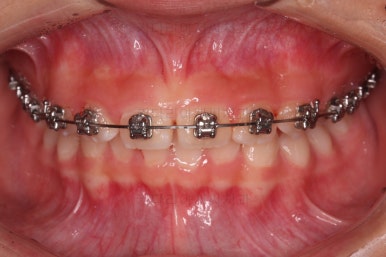

앞니의 각도가 앞으로 살아난 것이 보이실 거에요.

자연스럽게 과개교합 경향도 개선되어 어금니로 물었을 때 아래 앞니가 점점 보이기 시작하네요.

과개교합, 옥니, 앵글씨 2급 부정교합 모두 좋아지고 있어요.

앞니 각도가 매우 좋아졌고요.(옥니 개선) 위아래 앞니가 덮는 정도도 개선이 되었어요.(과개교합, 딥바이트)

엉성했던 어금니 맞물림도 매우 좋아졌어요.(앵글씨 2급 부정교합 개선)